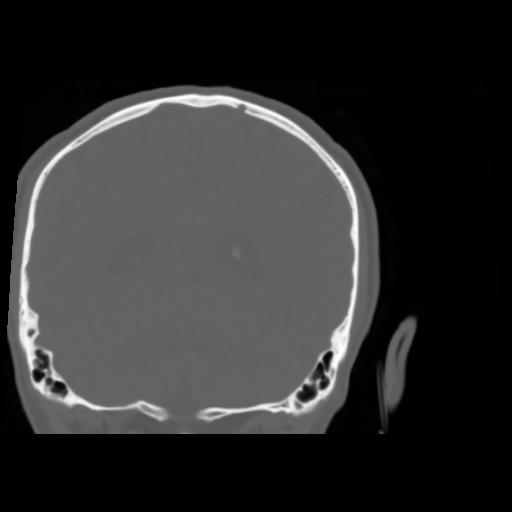

5 CEREBRO,,Coronal,3.000,CEREBRO,Coronal,